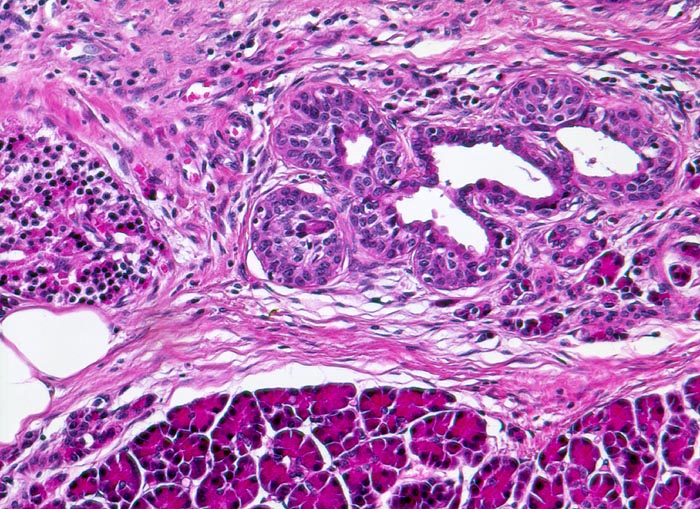

Bei einer Schädigung des Gangepithels und der Gangwände wie bei hereditärer oder Autoimmunpankreatitis entwickelt sich primär eine periduktale Fibrose.

Im Gegensatz zum duktalen Adenokarzinom ist das erhaltene Parenchym bei der chronischen Pankreatitis lobulär angeordnet. Drüsenepithelien zeigen keine Atypien. Karzinomverdächtig sind irregulär infiltrierende atypische Drüsen, atypische Drüsen in unmittelbarer Nachbarschaft von grösseren Gefässen ohne dazwischenliegende Azini, Perineuralscheideninvasion, rupturierte oder inkomplette Drüsen, und Drüsen mit luminalem nekrotischem Detritus.

Breite Bänder von sklerosiertem zellarmem Bindegewebe verlaufen zwischen den Läppchen.

Atrophie des exokrinen Pankreas.

Erhaltene Inseln und Gangstrukturen.

Spärliches chronisches Entzündungsinfiltrat.